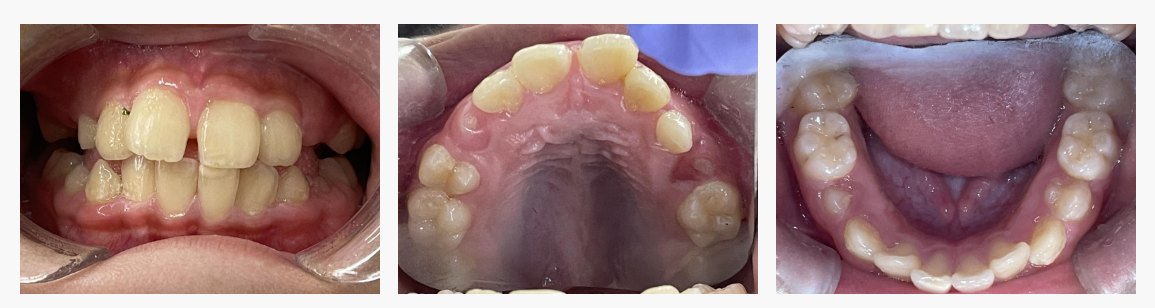

▼ Before(治療前)

初診時の状態

・上の前歯が前方に突出している

・口を閉じにくく、前歯が目立ちやすい

・成長期に入り、今後さらに前突が強くなる可能性

“これからの成長次第で、見た目・噛み合わせの両面に影響が出やすい状態”でした。

■診断名・初診時の状態

診断名:上顎前突(じょうがくぜんとつ)

初診時の診察では、

・上顎の前歯が前方へ傾斜

・口元が突出して見えやすい

・噛み合わせのバランスが崩れやすい状態

などの所見があり、

歯並びだけでなく、成長方向や口元のバランスにも配慮が必要な状態でした。